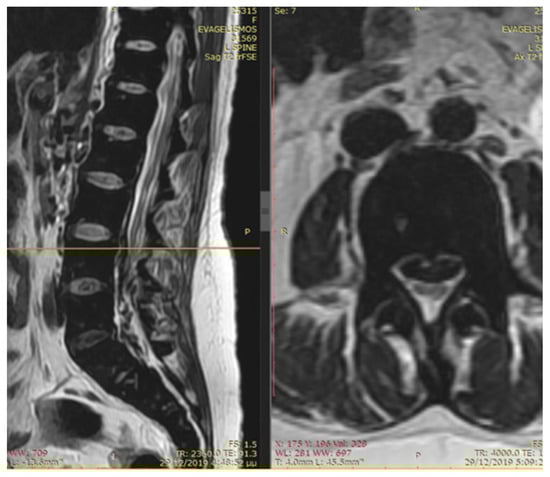

The patient noted a gradual improvement in neurological manifestations related to mobility and sensitivity. Upon discharge, she continued self-catheterization due to incomplete restoration of urination. Subsequently, the patient maintained subcutaneous iron chelation treatment with deferoxamine at a dosage of 80 mg/kg. Severe aplasia occurred two months after initiating hydroxyurea, leading to the discontinuation of both deferiprone and hydroxyurea until complete hematological recovery. Despite efforts to reintroduce hydroxyurea, the patient experienced aplasia again, prompting the decision to permanently cease this medication. Six months after the initial symptom onset, MRI findings indicated a reduction in mass and iron deposition (Figure 3 and Figure 4). The patient continued intensive iron chelation therapy with a combination of deferiprone and deferoxamine, resulting in a decreased iron load. Transfusions were maintained every 15 days with the goal of achieving hemoglobin levels above 10 g/dL. The patient achieved complete neurological recovery in the sensory and motor aspects, with only a minor improvement noted in neurogenic bladder dysfunction. Despite our patient experiencing severe myocardial iron overload, she maintained satisfactory systolic function in both the left and right ventricles. There were no observed valvular or conduction abnormalities, and the volume overload resulting from hypertransfusion did not adversely affect her overall cardiac function.

Figure 4.

The MRI findings six months after the first appearance of symptoms showed a decrease in mass and iron deposition.